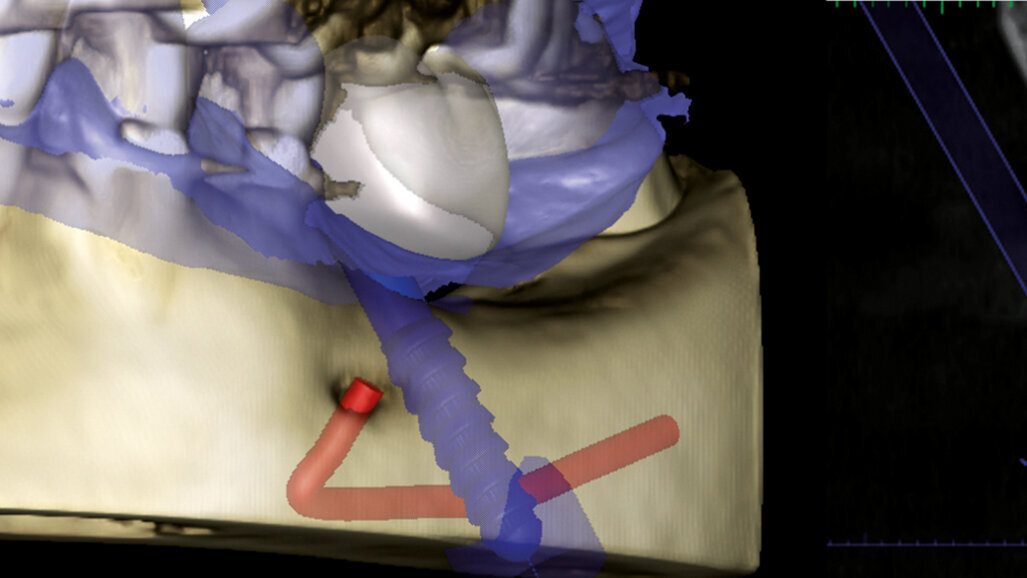

Na naše oddělení se dostavila pacientka, 52 let, s implantátem v místě 36, který byl zaveden na jiném pracovišti asi před 6 lety. Implantát vykazoval známky odhojení. Na OPG (ProMax, Planmeca) byl patrný velký úbytek kosti v okolí implantátu způsobený periimplantitidou (obr. 2). Proto byl implantát odstraněn, defekt byl exkochleován. Po 3 měsících bylo zhotovené CBCT (ProMax, Planmeca) pro plánování náhrady implantátu (obr. 3). Po zvážení všech možností (vertikální augmentace, short implant) jsme se rozhodli k zavedení tilted implantátu, který bude zaveden tak, aby míjel průběh mandibulárního kanálu (obr. 4). CBCT sken nám pomohl přesněji určit polohu mandibulárního kanálu. V programu jsem si následně vybral vhodný průměr i délku implantátu a určil jeho polohu tak, aby se vyhnul průběhu kanálu a zároveň respektoval aktuální nabídku kosti. Je velmi důležité podívat se na situaci z různých pohledů, abychom se ujistili, že jsme ošetření správně naplánovali.

Plánovaná pozice implantátu BioniQ v blízkosti mandibulárního kanálu.